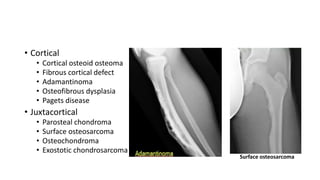

• Cortical

• Cortical osteoid osteoma

• Fibrous cortical defect

• Adamantinoma

• Osteofibrous dysplasia

• Pagets disease

• Juxtacortical

• Parosteal chondroma

• Surface osteosarcoma

• Osteochondroma

• Exostotic chondrosarcoma

Surface osteosarcoma